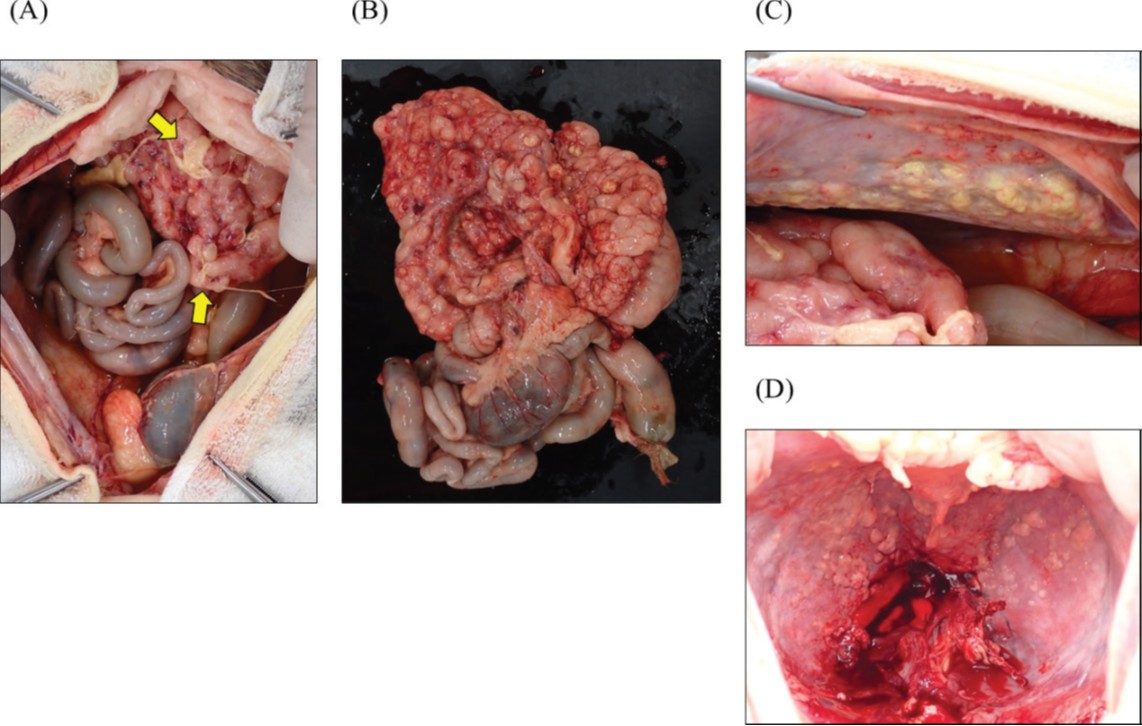

在获得主人同意后,于死亡当天进行了尸检。肉眼观察显示,存在严重的腹水,且少量纤维素附着于腹腔器官的浆膜面(下图A)。大网膜、小网膜和肠系膜增厚且质地坚硬,伴有多个结节形成(下图B)。胰腺和上段小肠被这些腹膜组织覆盖,并在上腹部形成一个肿块,导致活动性丧失。腹壁和膈肌腹侧观察到大量不规则结节(下图C-D)。在全面检查中未发现腹腔淋巴结。

↑ 尸检的肉眼观察结果。(A)不规则增厚的腹膜(大网膜、小网膜和肠系膜)在上腹部形成了一个肿块。在腹腔器官的浆膜表面观察到少量纤维素沉积(箭头)。(B)上段小肠被不规则增厚的腹膜覆盖,导致活动性丧失。(C)左侧腹壁和(D)膈肌腹侧观察到多个白色至黄白色的结节,大小为3−5毫米。